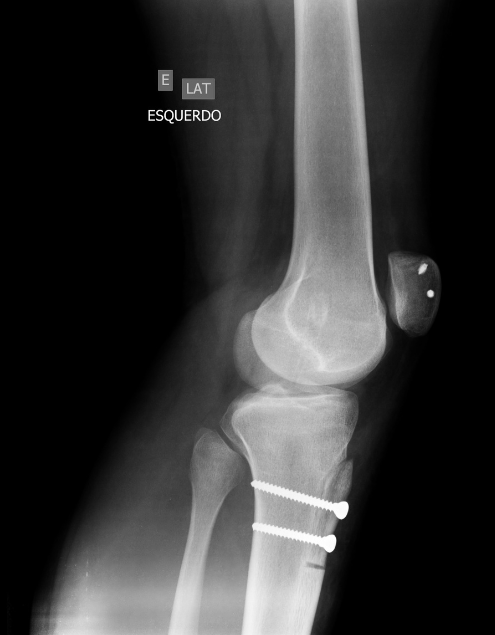

Discutiremos algumas das condições ortopédicas mais comuns, como a osteoartrite, a artrite reumatoide, as fraturas ósseas e as lesões ligamentares. Abordaremos também os métodos de diagnóstico e as opções de tratamento disponíveis para pacientes que enfrentam essas condições.

A cirurgia ortopédica desempenha um papel essencial na correção de problemas musculoesqueléticos graves. Vamos explorar os diferentes tipos de cirurgias ortopédicas, desde a substituição de articulações até a correção de deformidades. Além disso, discutiremos a importância da reabilitação após a cirurgia para uma recuperação bem-sucedida.